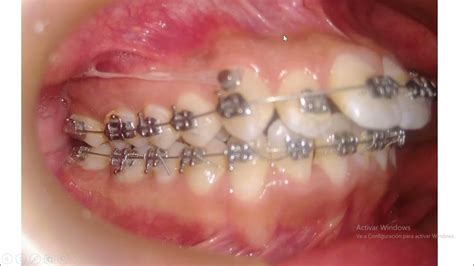

- Brackets Tradicionales o Alineadores Invisibles (Invisalign): Los brackets tradicionales, hechos de metal o cerámica, son aparatos fijos que aplican presión constante sobre los dientes para moverlos gradualmente a su posición correcta. Por otro lado, los alineadores invisibles como Invisalign son una alternativa estética y cómoda para corregir la alineación de los dientes. Estos alineadores son removibles y casi imperceptibles, lo que los convierte en una opción popular entre los pacientes adultos.